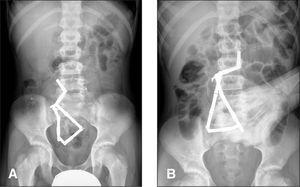

La radiografía de abdomen el día del ingreso mostraba 8 piezas radioopacas en mesogastrio; en la radiografía 48 h después, éstas no habían modificado su localización y existía una leve distensión de asas de delgado, por lo que se decidió intervenir al paciente (fig. 1). El contacto entre sí de los imanes que se encontraban en cámara gástrica y asas vecinas había producido dos fístulas gastroyeyunales a través del meso del colon y otra más a 75 cm del asa fija; existían también perforaciones cubiertas a 30, 75, 120 y 200 cm del asa fija, siendo el número total de 13 (figs. 2-4). No había líquido libre, pero sí un imán en saco de Douglas.

Figura 1. Radiografía al ingreso(A)y 48 h después(B).